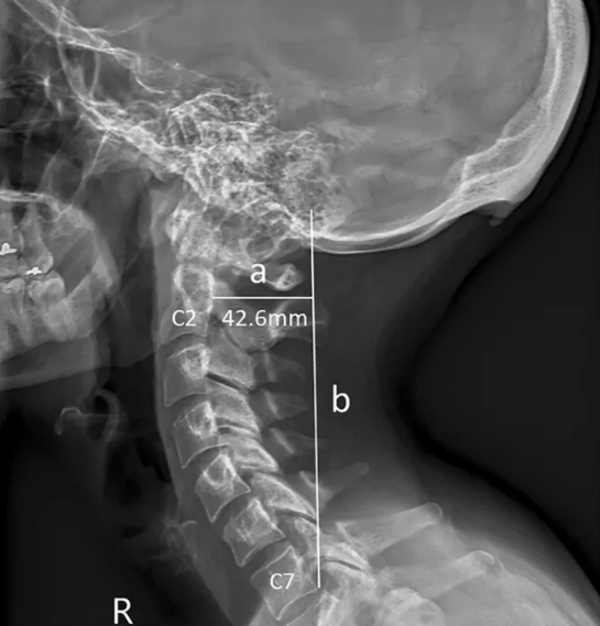

2. Avustralya’daki Sunshine Coast Üniversitesi’den bilim adamları Dr. David Shahar ve Prof. Mark Sayers, 18-30 yaş arasındaki 218 kişinin röntgen çekimlerini inceledi. Yapılan araştırmalar sonucu röntgen çekilen kişilerin neredeyse yarısının kafatası şeklinin yoğun cep telefonu ve tablet kullanımına bağlı olarak ‘değiştiği’, boynuzumsu bir çıkıntıya benzediği belirtildi.

Avustralya’daki Sunshine Coast Üniversitesi’den bilim adamları Dr. David Shahar ve Prof. Mark Sayers, 18-30 yaş arasındaki 218 kişinin röntgen çekimlerini inceledi. Yapılan araştırmalar sonucu röntgen çekilen kişilerin neredeyse yarısının kafatası şeklinin yoğun cep telefonu ve tablet kullanımına bağlı olarak ‘değiştiği’, boynuzumsu bir çıkıntıya benzediği belirtildi.

6. Ensenin üstünde sivrilen 10-30 milimetre arasında değişen çıkıntıya, &#8216;dış oksipital kabartı&#8217; deniyor. Dış oksipital kabartıya, taşınabilir dijital cihazlar yaygınlaşmaya başlamadan önce daha çok yaşlı insanlarda rastlandığı, gençlerde ise oldukça nadiren rastlandığı belirtiliyor.

Ensenin üstünde sivrilen 10-30 milimetre arasında değişen çıkıntıya, ‘dış oksipital kabartı’ deniyor. Dış oksipital kabartıya, taşınabilir dijital cihazlar yaygınlaşmaya başlamadan önce daha çok yaşlı insanlarda rastlandığı, gençlerde ise oldukça nadiren rastlandığı belirtiliyor.

7. Kafatasındaki çıkıntının, iskelet yapısında uzun süre baskıya maruz kalmış kişilerde rastlanması hesaba katıldığında, uzun süre cep telefonu ekranına bakmanın da benzer etkiyi yarattığı söylenebilir.

Kafatasındaki çıkıntının, iskelet yapısında uzun süre baskıya maruz kalmış kişilerde rastlanması hesaba katıldığında, uzun süre cep telefonu ekranına bakmanın da benzer etkiyi yarattığı söylenebilir.